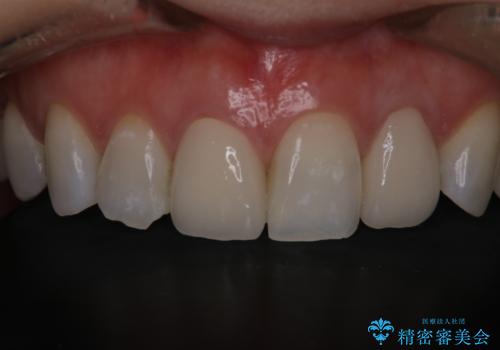

歯茎の出来もながなくなり、患者様にセラミックの色も満足いただけました。